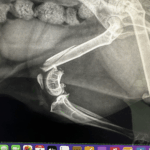

オレンジ色のマル部分の歯を歯科レントゲンで撮影してみると、

緑色のマルの写真になります。骨が溶けてしまい、歯の根っこがみえてしまっています。

その歯に器具を差し込むと、貫通しているのが分かります。残念ながらこの歯は、抜歯処置になります。